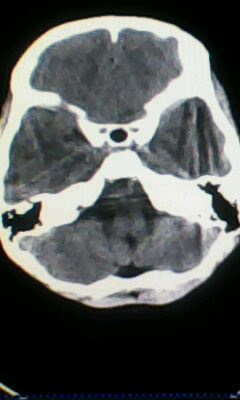

标题: PED3324:男 10岁 右侧 眼不自主抽动 自感颈部不适 [打印本页]

标题: PED3324:男 10岁 右侧 眼不自主抽动 自感颈部不适

蛛网膜下腔出血。

蛛网膜下腔出血可能。

颅脑ct轴位平扫颅内未见明确异常;建议必要时行mri检查。

窗调的不好,图像感觉怪怪的,不好说有什么明显异常,可建议mri检查。

颅脑ct轴位平扫颅内未见明确异常。